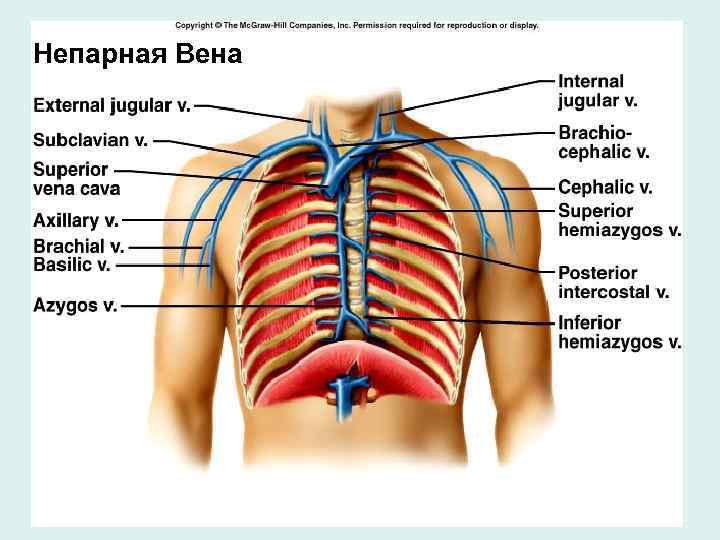

Верхняя полая вена • Образуется от слияния правой и левой плечеголовных вен • Притоки: непарная вена (справа), мелкие средостенные и перикардиальные вены (слева)

Непарная Вена • истоки: правая восходящая поясничная вена • Притоки: задние межреберные вены, вены позвоночных сплетений, пищеводные, бронхиальные, перикардиальные, медиастинальные, полунепарная вена

Непарная Вена

Непарная Вена